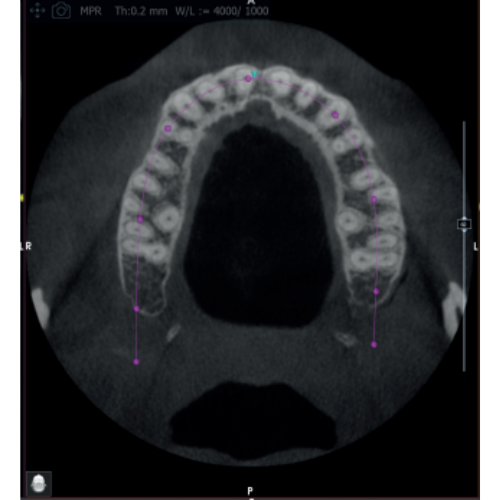

X-MIND® optima 3D represents the perfect combination of advanced hardware technology, enclosed in a lightweight and compact design and next-generation software, RealGuide™ 5.4, bringing the benefits of Artificial Intelligence into every step of patient care, from a precise diagnosis to more effective treatments and patient communication.

- Field Of View: 5x5, 8.5x5, 8.5x9, 12x10

- 2D and 3D Imaging

- Panoramic

- Multi FOV

- Adjustable FOV